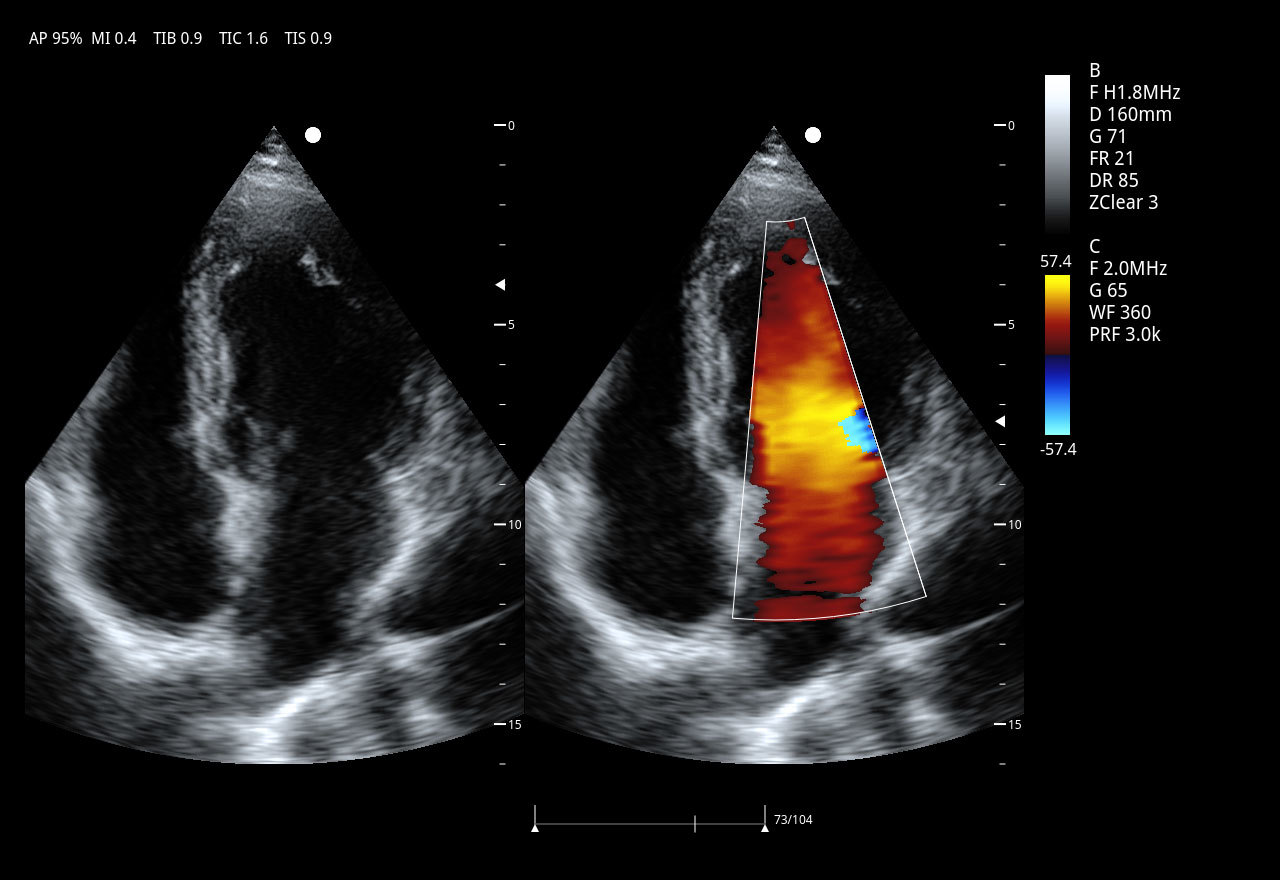

Imágenes clínicas extraordinarias

El Doppler Color ViV 20 es un ecógrafo de nueva generación diseñado para ofrecer una experiencia clínica superior con un equilibrio perfecto entre rendimiento, durabilidad y accesibilidad. Su arquitectura avanzada proporciona imágenes claras y precisas, permitiendo diagnósticos confiables en aplicaciones como abdomen, ginecología, vascular, partes blandas y más.

| Aplicaciones | Cardiología, abdomen, vasos sanguíneos, estudios generales |

Imágenes armónicas por inversión de pulso PIHI

Con PIHI, se transmiten simultáneamente dos ondas de pulso con fase opuesta, se activa el procesamiento de superposición de ecos y se cancela la señal de las formas de onda fundamentales, generando ondas armónicas de 6 dB. PIHI reduce eficazmente el ruido de moteado y mejora significativamente el contraste y la resolución de la imagen.